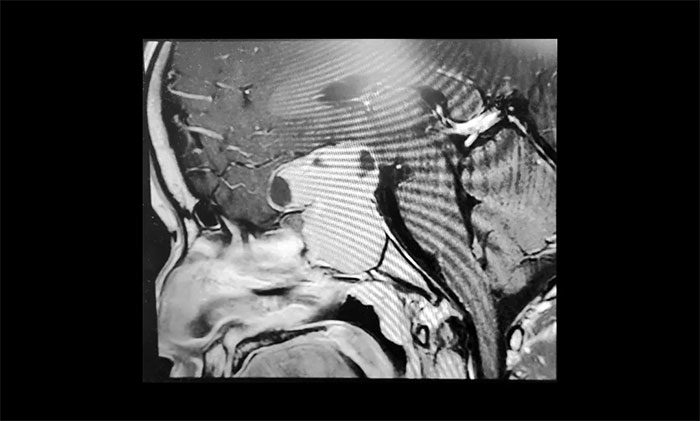

为了进一步确定瘤体的位置和大小,当即进行了鞍区MRI平扫+增强。影像显示,蝶鞍显著扩大,鞍区见一“塔样”肿块灶,病变总矢横高径约3.5×4.5×5cm。瘤体向鞍上生长,占据鞍上池,明显推移视交叉、分界模糊,三脑室前下部受压变形。鞍底塌陷、蝶窦填充;侵及包绕两侧海绵窦约1/2,海绵窦向外侧移位。

一般来说,鞍区病变常采用经鼻蝶、经额下、和经翼点等入路进行手术。但以上入路手术的缺陷与优点都同样突出,而且对受术者的身体条件有一定要求。经过综合权衡,结合小刘的自身的身体条件和病症特点,李士其教授最终锁定了经眉弓眶上锁孔手术,以期借助微创技术切除肿瘤,尽可能降低脑部损伤。

眶上锁孔入路与传统的弧形切口翼点入路相比,皮肤损伤更小,眉弓切口更靠近颅底,能排空脑池脑脊液,开放颅内自然存在的解剖间隙,因为鞍上区域的后方为中脑,两侧为颞叶,经其他入路有可能牵拉上述脑组织,经眶上入路无需牵拉脑组织即可显露鞍上区域,从而减少对额、颞叶的牵拉和嗅束损伤。同时根据肿瘤不同位置可调整骨窗位置,通过小骨窗远距离获得对病灶足够大的显露。

3月中旬,经过充分的术前准备,并征得家属同意后,由黄秀夫医生协助,李士其教授正式为小刘行经眉弓眶上锁孔手术。凭借娴熟的显微外科手术技巧,丰富的手术经验,熟练的显微神经解剖,在充分保护好海绵窦、颈内动脉、视神经等结构前提下,李士其教授在错综复杂的神经血管狭窄间隙中,逐步分块切除肿物,仔细刮除肿瘤,最终将肿瘤全部切除,手术顺利完成。

术后,小刘左眼视力有所改观,右眼由于压迫损伤,视力改善还不明显。